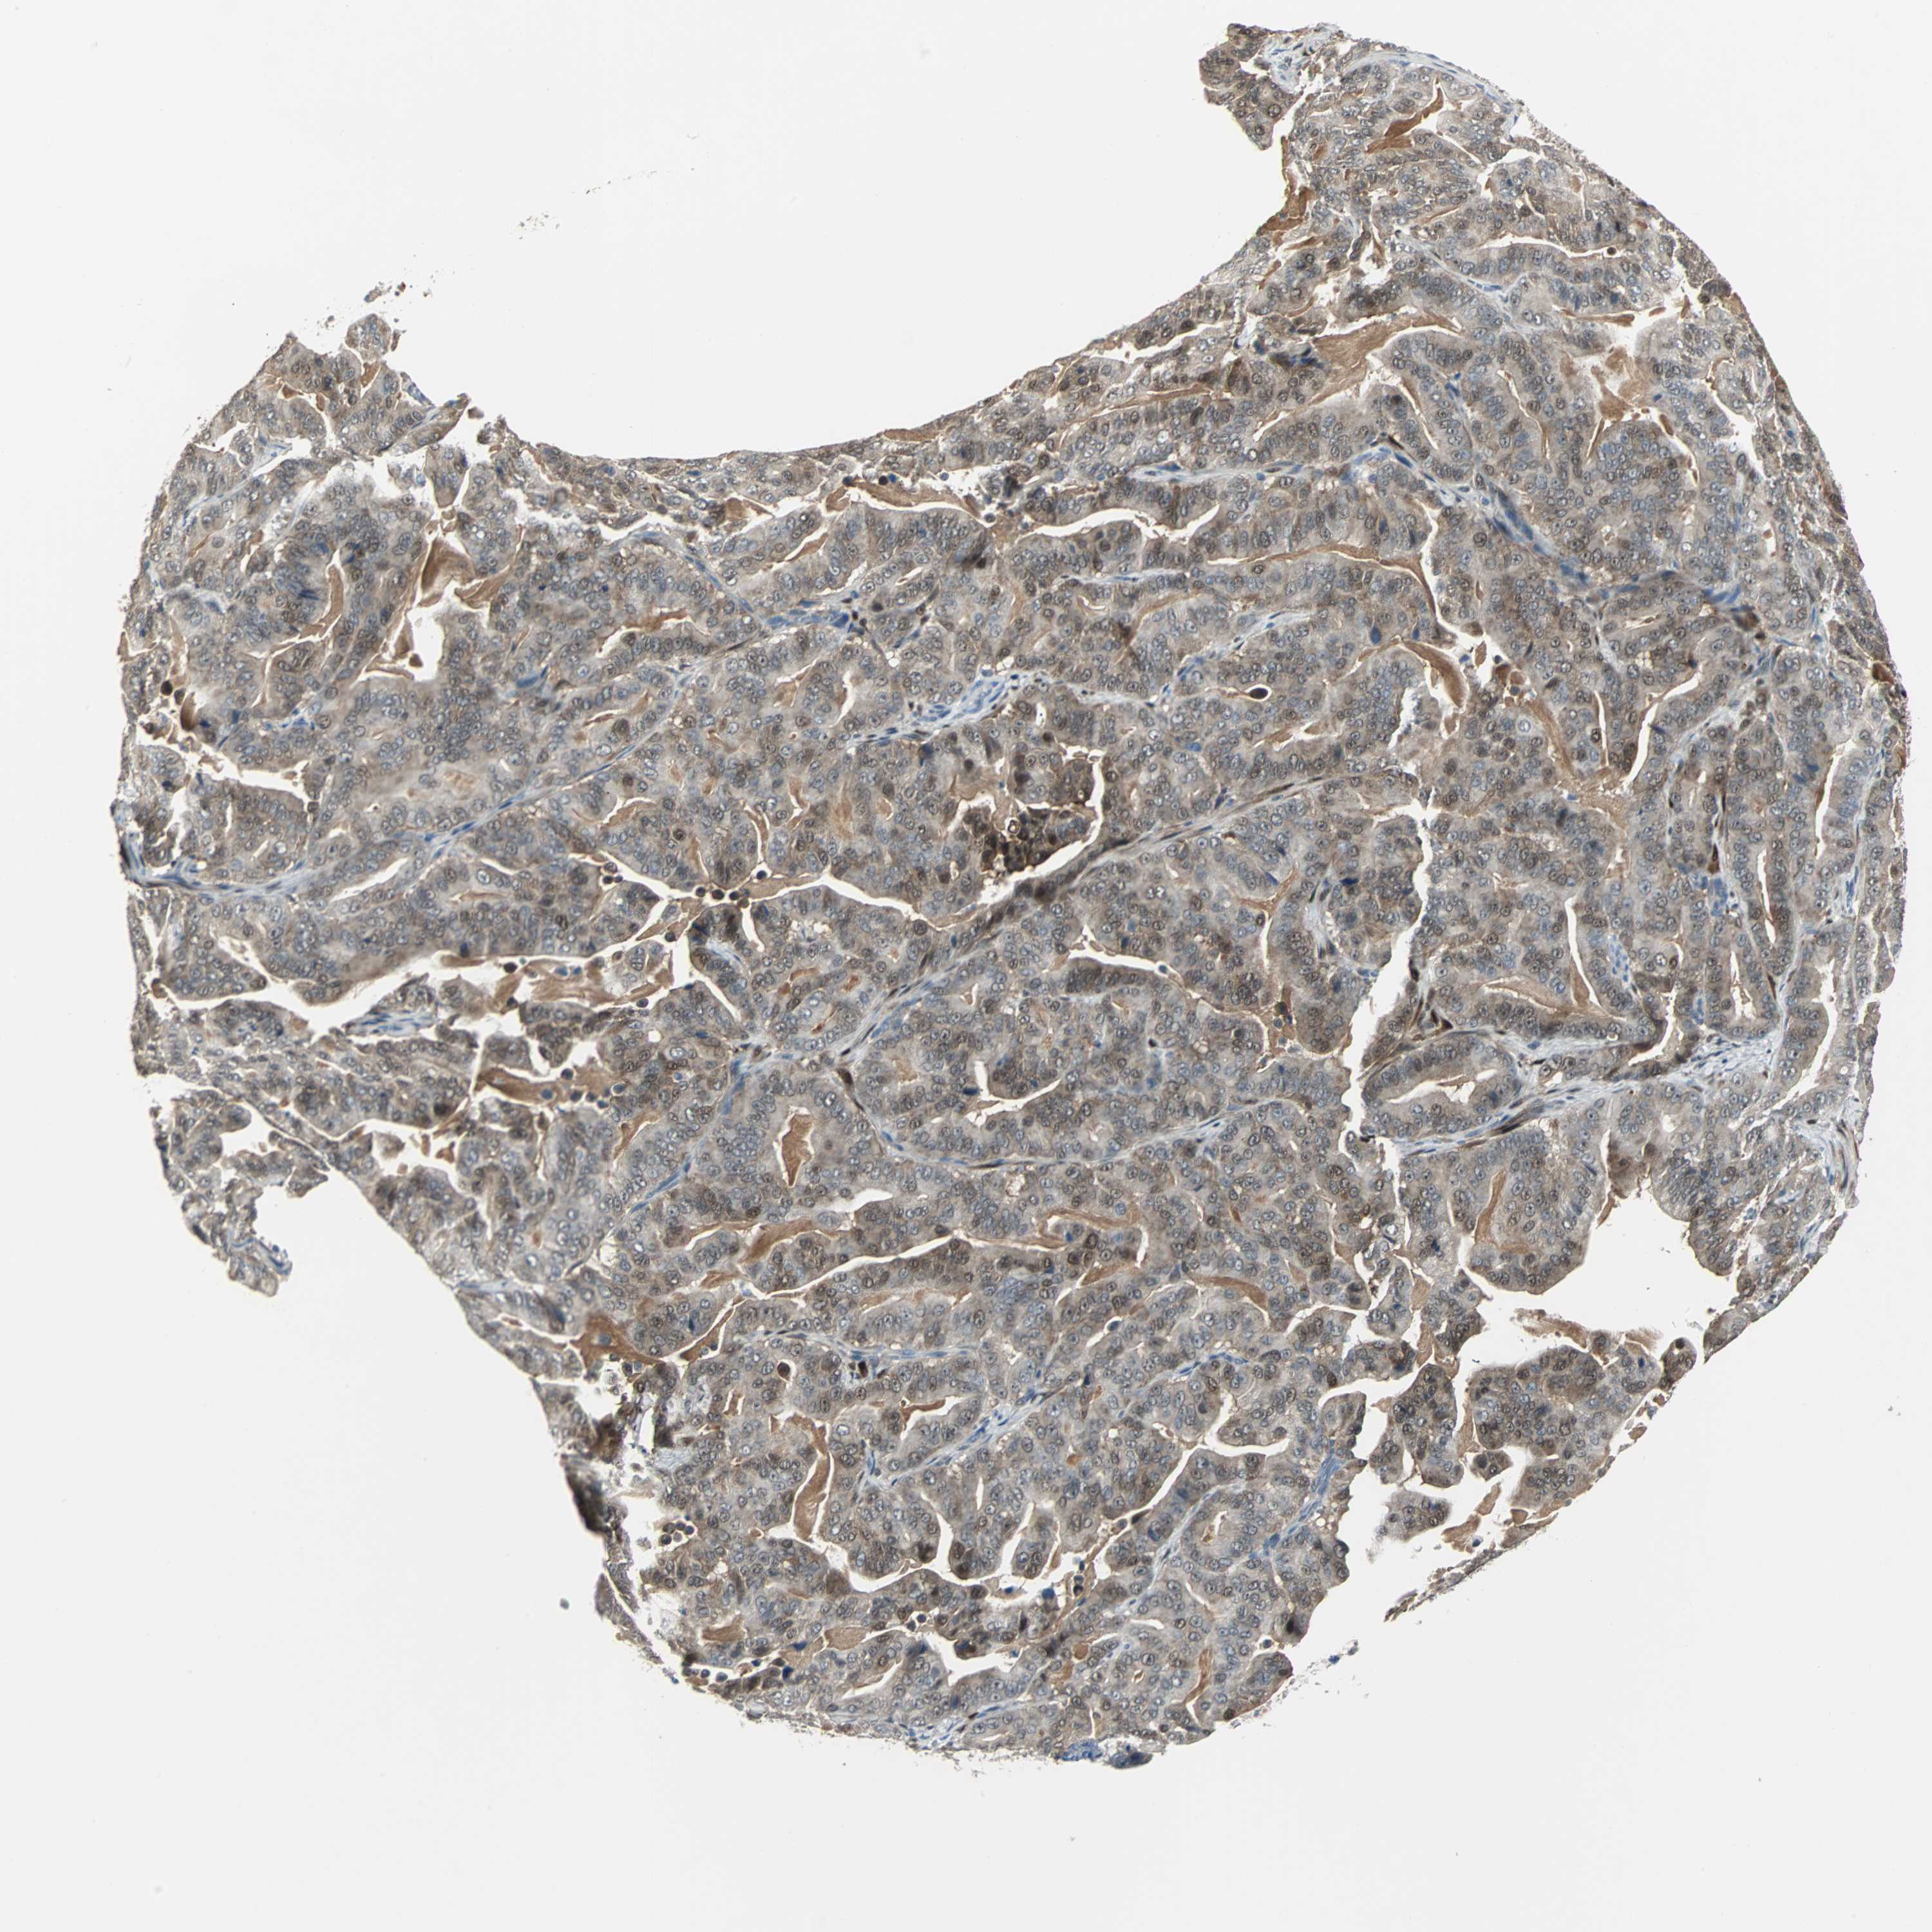

PANCREATIC CANCER - Protein expressioni

A mouse-over function shows sample information and annotation data. Click on an image to view it in a full screen mode. Samples can be filtered based on level of antibody staining by selecting one or several of the following categories: high, medium, low and not detected. The assay and annotation is described here.

Note that samples used for immunohistochemistry by the Human Protein Atlas do not correspond to samples in the TCGA dataset.

Antibody stainingi

Antibody staining in the annotated cell types in the current human tissue is reported as not detected, low, medium, or high, based on conventional immunohistochemistry profiling in selected tissues. This score is based on the combination of the staining intensity and fraction of stained cells.

Each image is clickable and will lead to virtual microscopy that enables deeper exploration of all samples and also displays staining intensity scores, fraction scores and subcellular localization as well as patient and tissue information for each sample.

Antibody HPA005922

Antibody HPA006028

Antibody CAB008368

Staining

High

Medium

Low

Not detected

Intensity

Strong

Moderate

Weak

Negative

Quantity

>75%

75%-25%

<25%

None

Location

Nuclear

Cytoplasmic/membranous

Cytoplasmic/membranous,nuclear

Adenocarcinoma, NOS

Adenocarcinoma, metastatic, NOS